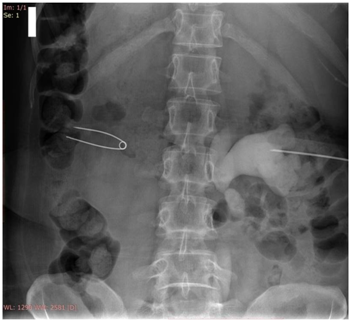

Precise point of entry was confirmed by a performing a nephrostogram and once the access into target calyx was confirmed the needle was exchanged over 0.035 Terumo guide wire. The tract was serially dilated, catheter introduced and guide removed after confirming correct placement of catheter tip. The nephrostomy tube was secured and urobag attached. Post procedure nephrostogram was performed Figure 2.

Figure 2a Radiograph showing the puncture needle in the dilated opacified PCS.

Figure 2b Radiograph showing the guidewire in the opacified PCS and the ureter with the needle in the PCS.

Figure 2c Radiograph showing dilator over the guidewire inside the opacified PCS.

Figure 2d Radiograph showing malecot’s catheter in the opacified PCS.